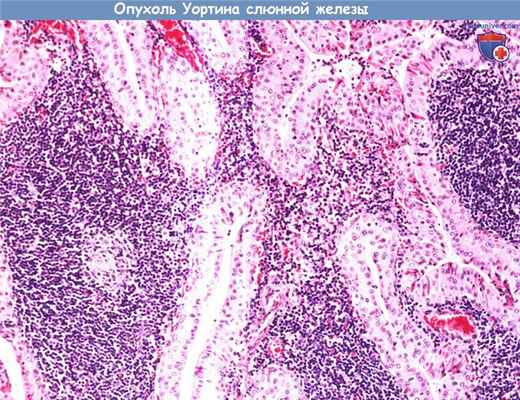

Опухоль Уортина (сосочковая кистаденолимфома) составляет примерно 3,5% всех эпителиальных опухолей слюнных желез. Встречается практически исключительно в околоушной слюнной железе. Может иметь дольчатое строение, иногда двусторонняя.

Опухоль Уортина (сосочковая кистаденолимфома) составляет примерно 3,5% всех эпителиальных опухолей слюнных желез.

Встречается практически исключительно в околоушной слюнной железе. Может иметь дольчатое строение, иногда двусторонняя.

При микроскопии опухоль имеет кистозно-сосочковое строение. Эпителиальные клетки с онкоцитарной метаплазией (большое количество цитоплазматических митохондрий,

розовая цитоплазма с частыми включениями) располагаются в два ряда, формируя сосочковые структуры, которые перемежаются с участками лимфоидной гиперплазии.

После удаления рецидивирует редко.